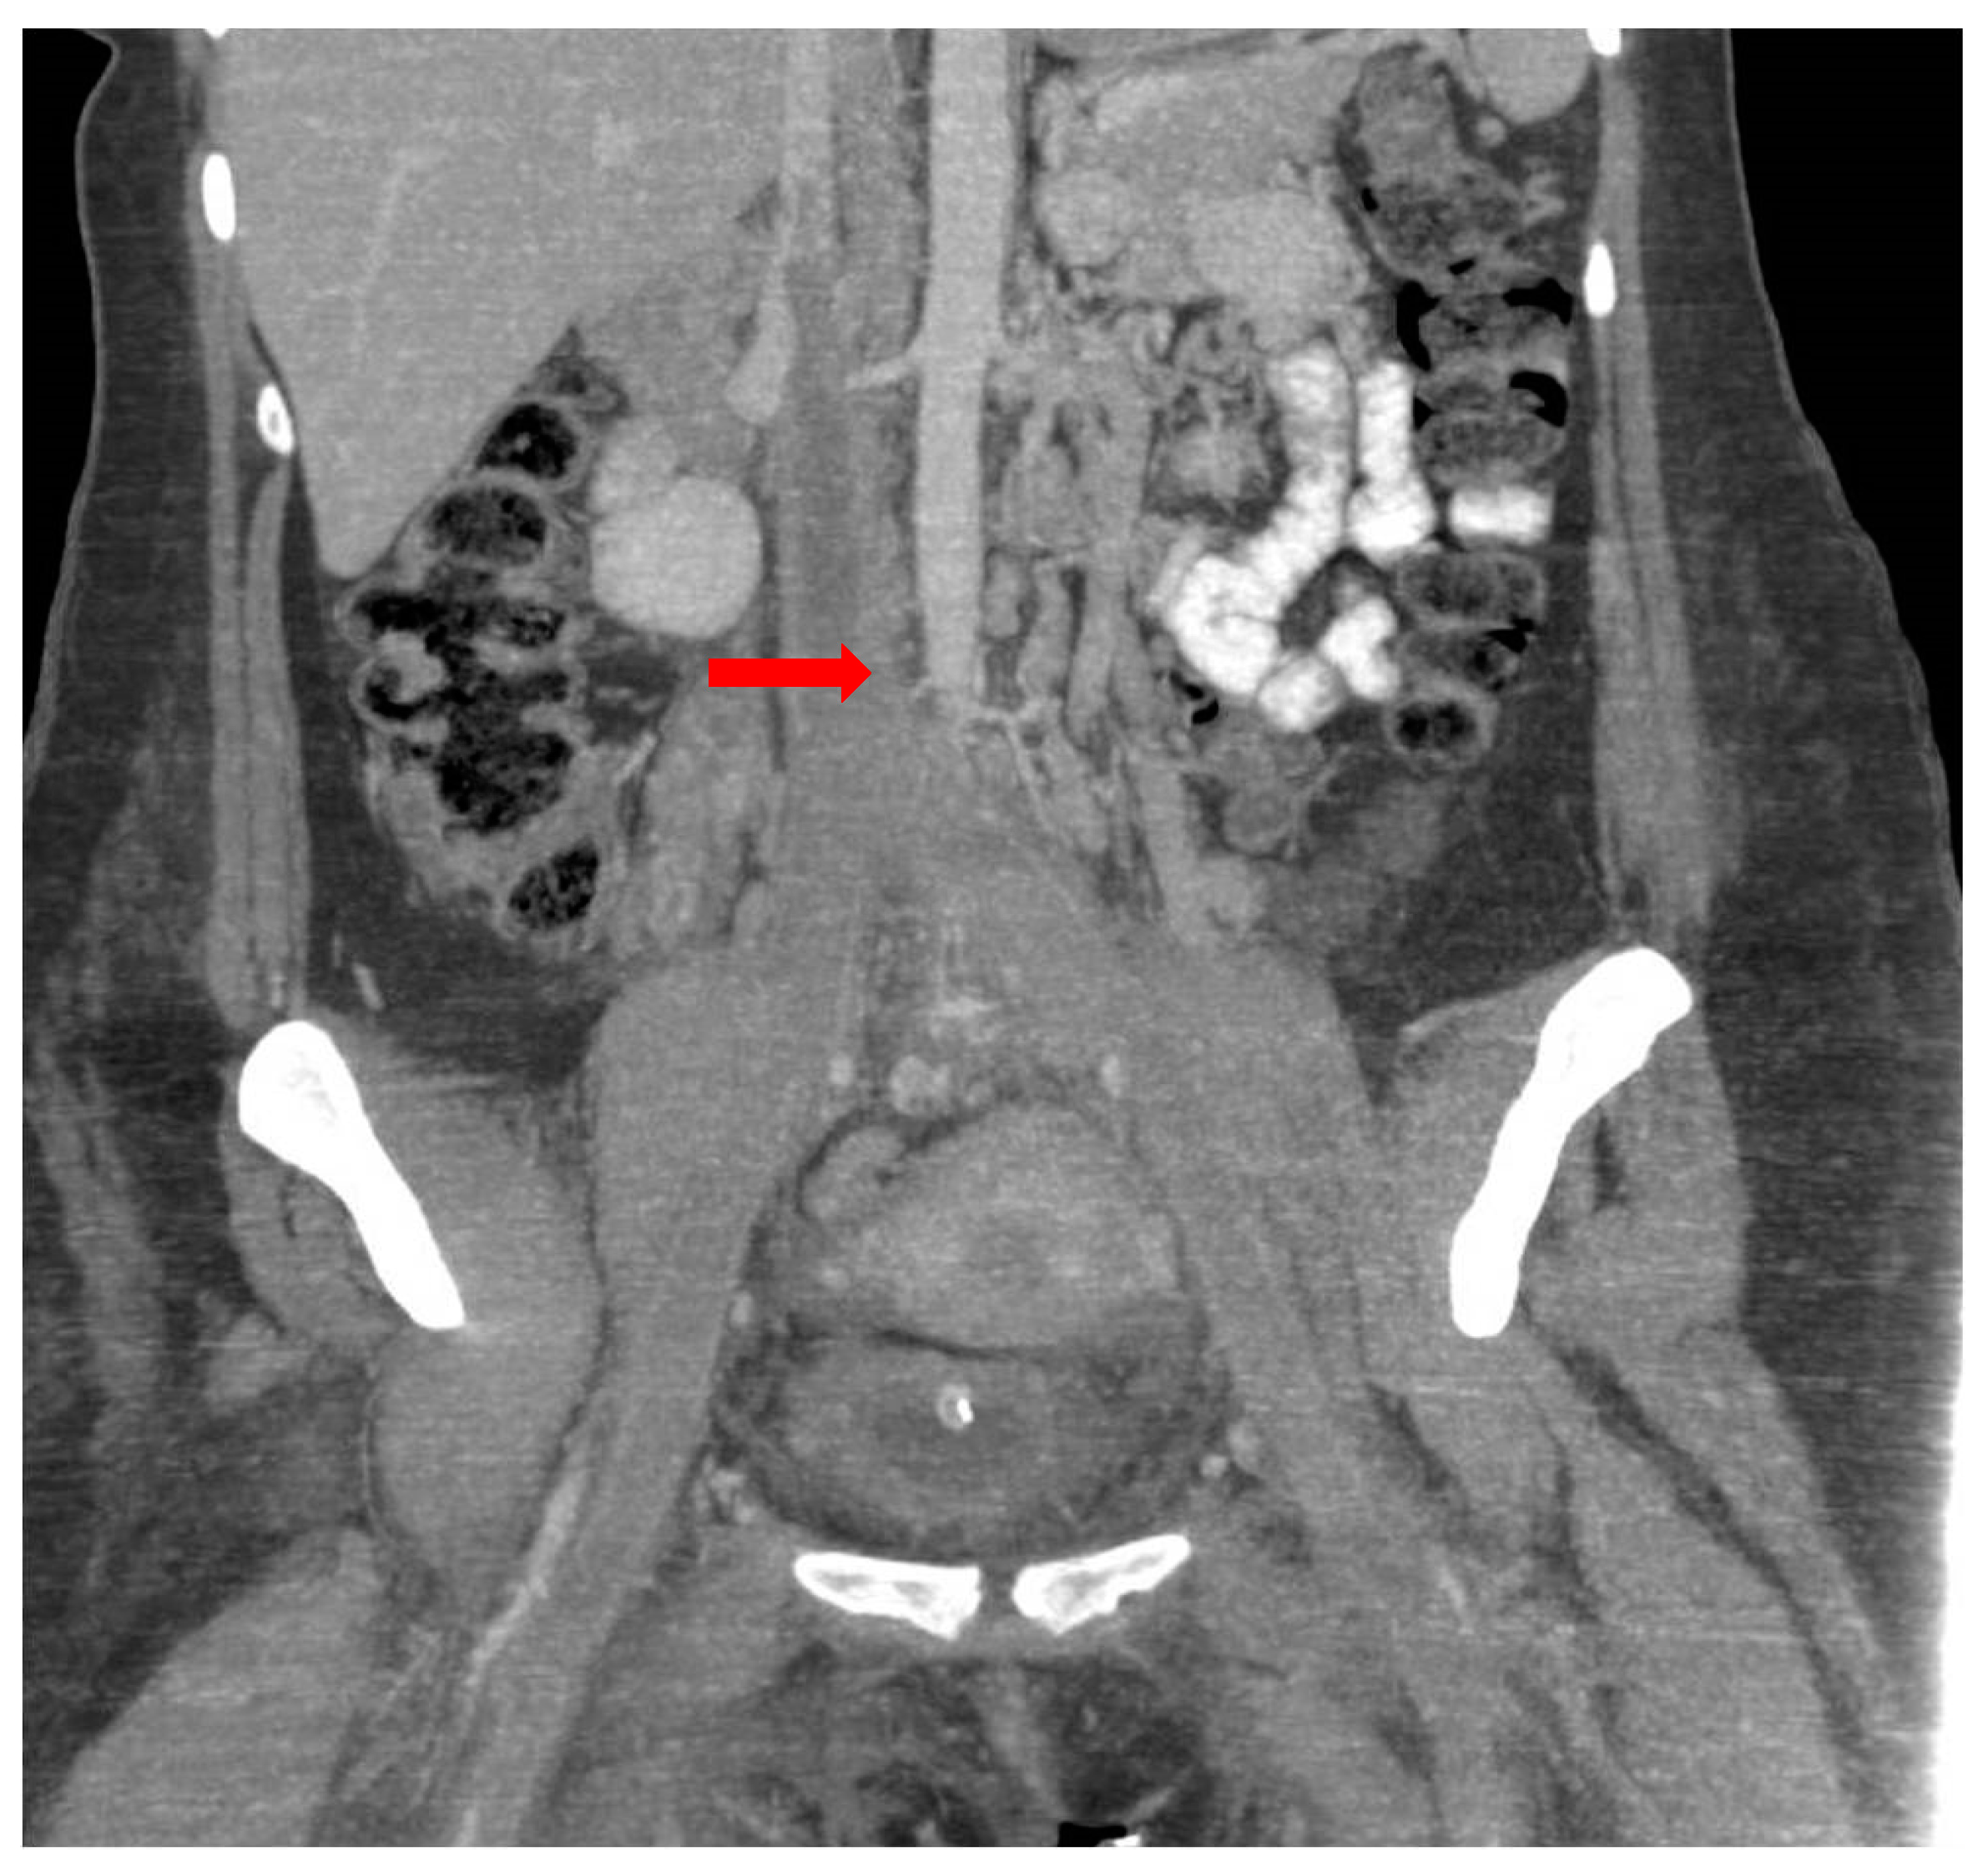

The results of the abdominal and pelvic computed tomography examination revealed venous thrombosis in the inferior cava vein with an extension to both the common iliac veins and internal and external iliac veins, and it also extended to the bilateral femoral veins (Figure 2). The pulmonary artery and its branches were completely opacified without signs of pulmonary thromboembolism. Additionally, minimal basal right pleural fluid was observed.

Figure 2. Venous thrombosis in inferior cava vein with extension to the common iliac veins and bilateral femoral veins (red arrow).